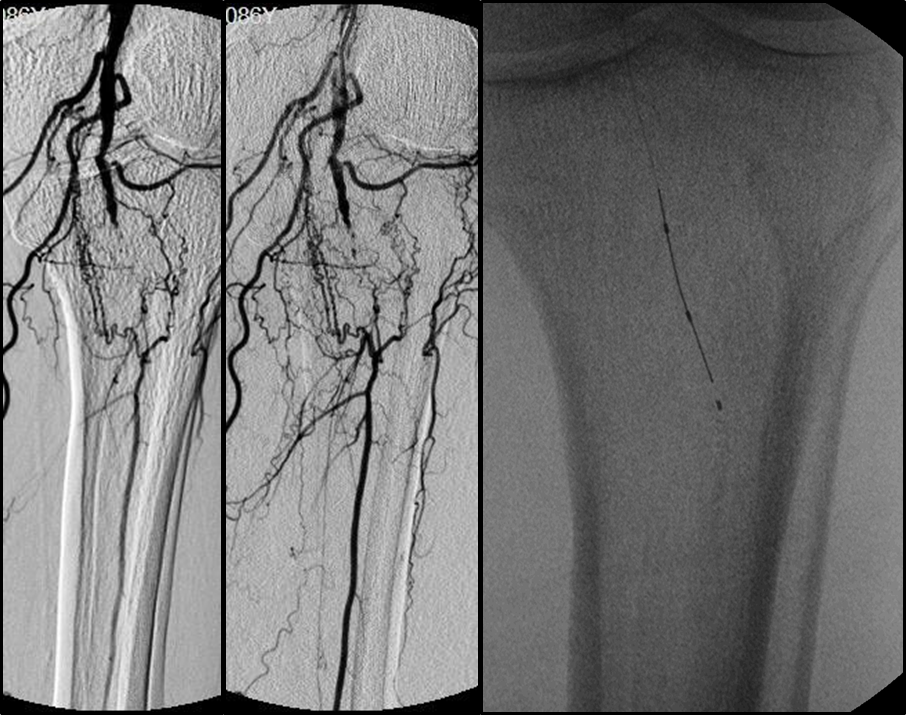

各分支 CTO 解剖特点

三大主要分支的CTO近端与远端常见位置:

总体特点:

膝下通常有单个或数个可见的流入道;

病变常为单个或多个CTO组合,总长度可达20cm;

部分患者存在踝上交通动脉或完整的踝下足底弓,为逆向开通提供可能。